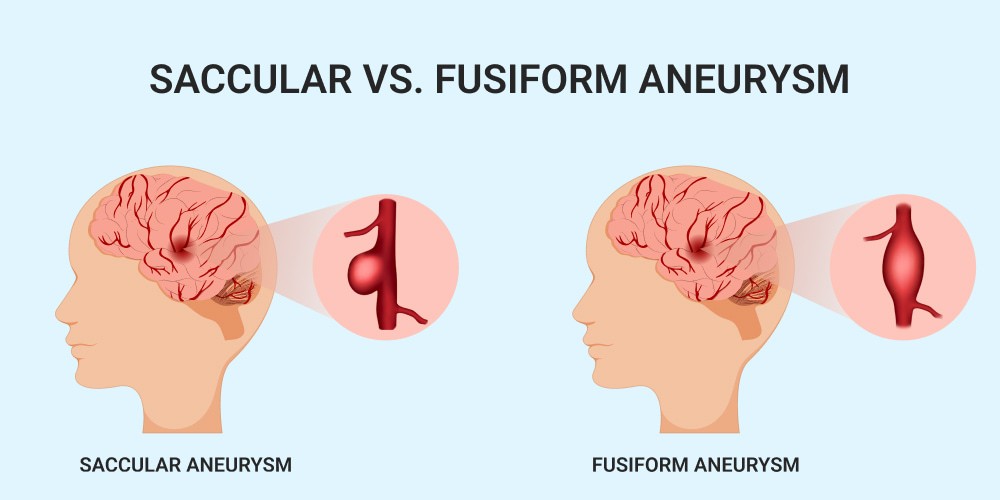

Um aneurisma cerebral é uma pequena “bolha” que se forma na parede de um vaso do cérebro. Essa parte da parede fica mais fina e mais frágil, como um ponto de fraqueza no encanamento.

É quando existe uma parte mais fraca na parede do vaso do cérebro, que forma uma bolha, como se fosse uma bexiga ou um ponto frágil no cano.

Dizemos aneurisma não roto quando essa “bexiga” não estourou.